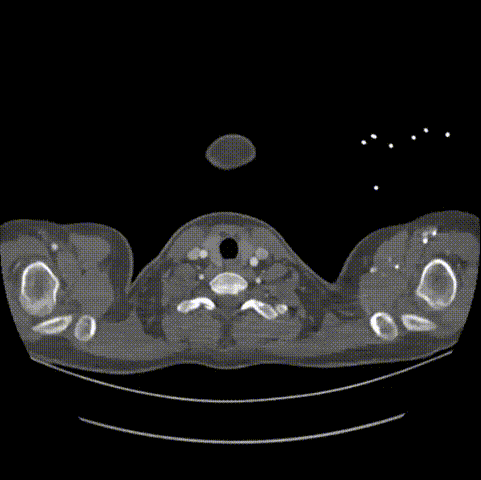

锚定区距离

血管直径

患者女性,15岁,因意外高空坠落收治入院。患者入院后行CTA检查,可见主动脉峡部局限夹层,小弯侧距离左锁骨动脉后缘锚定距离7.9mm,患者年纪小,主动脉直径较细。